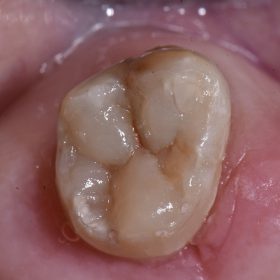

Composite Reconstruction of Teeth | Replacement Fillings | Cosmetic Dentist Auckland

Sometimes, crowning a tooth is not the only solution for structure replacement due to cavities or fractures. Here we see a case affected by old, leaking filling material and weakened, […]